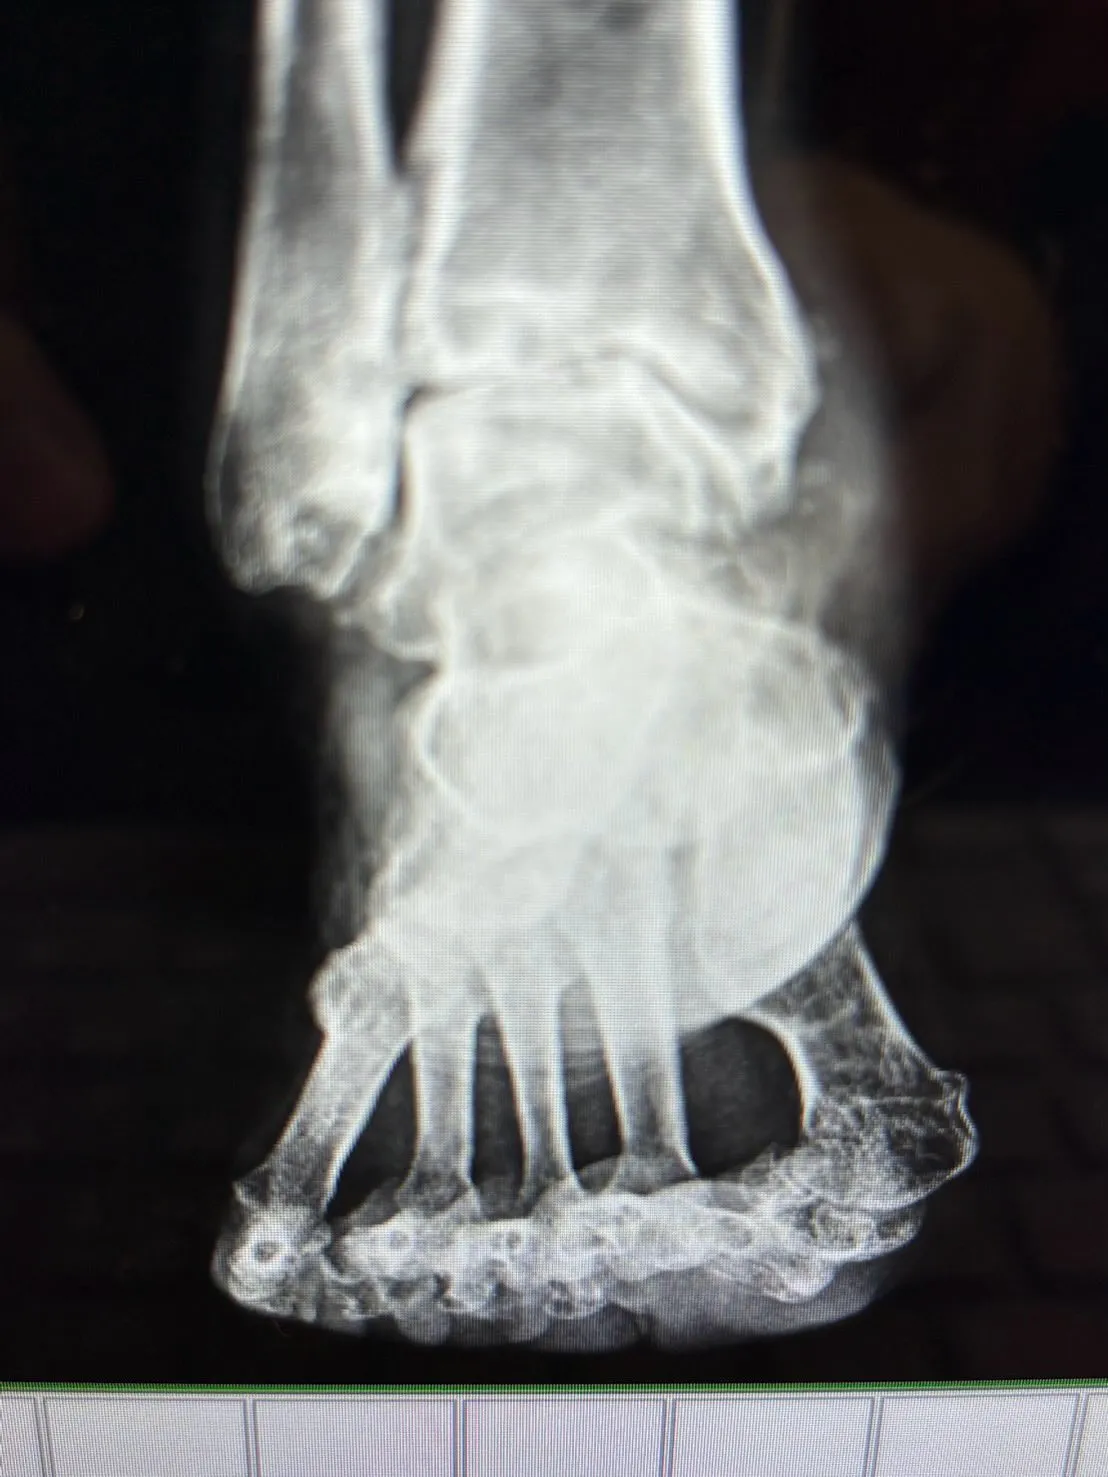

通っているお客様のレントゲン🩻 どれくらい酷い状態かわかるかな? 痛みなく歩けてることが奇跡✨